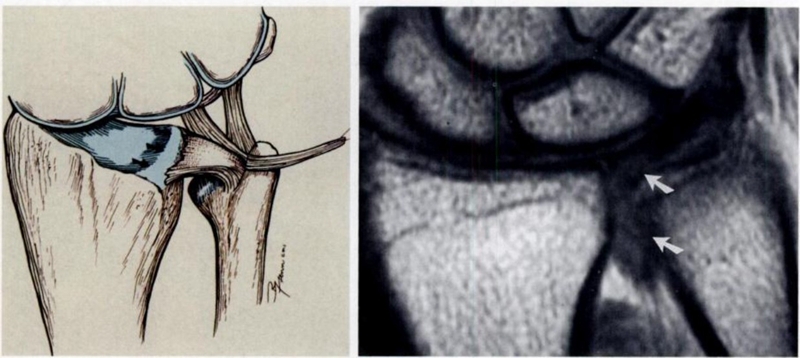

ⅠB,TFCC尺侧撕裂;TFC尺侧附着处信号增高